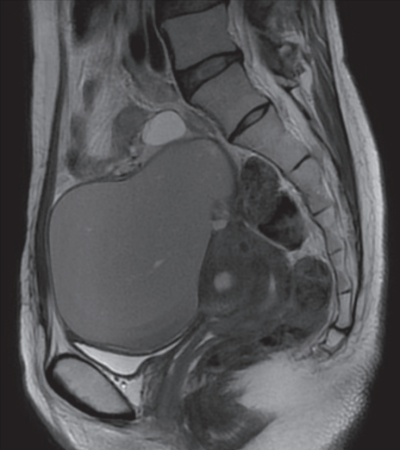

血液所見:赤血球 390 万、Hb 10.8 g/dL、Ht 36 %、白血球 5,200、血小板 18 万。血液生化学所見: 総蛋白 6.8 g/dL、AST 28 U/L、ALT 22 U/L、CA19-9 32 U/mL(基準 37 以下)、CA125 52 U/mL(基準 35 以下)。骨盤部単純 MRI の T2 強調矢状断像を別に示す。